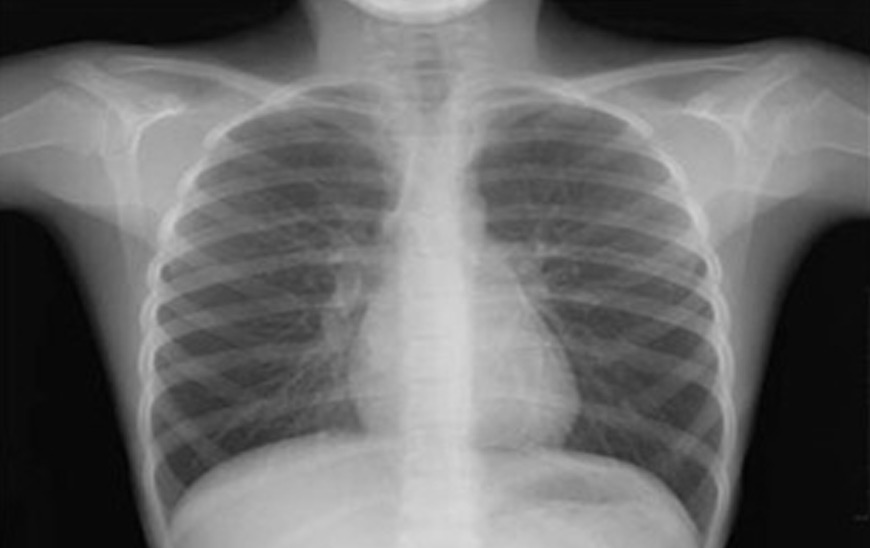

Disponemos de equipos móviles para realizar, en su domicilio, las radiografías que hayan sido solicitadas, (a realizar específicamente en el domicilio por imposibilidades del paciente), por un profesional médico exclusivamente, por lo que se deberá disponer, en todos los casos, de la orden escrita del mismo. Los estudios radiológicos a domicilio se realizan únicamente en casos de urgencia y cuando el paciente no pueda trasladarse por sus propios medios a un centro asistencial adecuado para realizarlos.

Radiografías que pueden realizarse en su domicilio: Tórax, frente. Mano, frente y perfil. Muslo, frente y perfil. Brazo, frente y perfil. Rodilla, frente y perfil. Codo, frente y perfil. Muñeca, frente y perfil. Tobillo, frente y perfil. Pierna, frente y perfil. Antebrazo, frente y perfil. Condicionadas al peso del paciente: radiografías de pelvis y caderas.

Disponemos de equipos móviles para realizar, en su domicilio, las radiografías que hayan sido solicitadas, (a realizar específicamente en el domicilio por imposibilidades del paciente), por un profesional médico exclusivamente